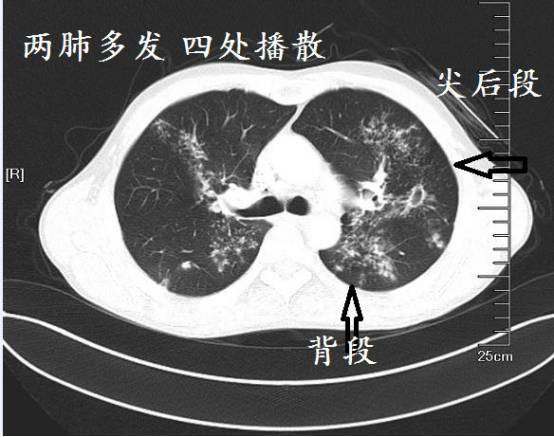

肺结核病影像特点是病变多发生在上叶的尖后段和下叶的背段,密度不均匀、边缘较清楚和变化较慢,易形成空洞和播散病灶。

好发部位

肺结核好发于上叶的尖后段和下叶的背段,这是肺结核最基本的特点!为什么结核容易长在这些地方,目前没有公认的理由。

可能因为人直立时,这些部位的血压相对低, 血液循环差,巨噬细胞减少,导致局部抵抗力低,并且,这些部位氧气多,结核是需氧菌,在上叶的尖后段和下叶的背段聚集,正所谓占尽天时地利。